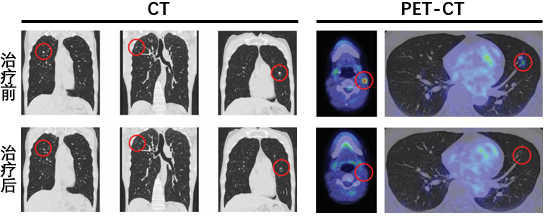

令人惊喜的是,治疗后,患者的病情迅速出现好转:肿瘤病灶不断缩小,转移灶逐渐消退,达到完全缓解。截至随访时间,患者的完全缓解状态已维持超过5年,无复发迹象。